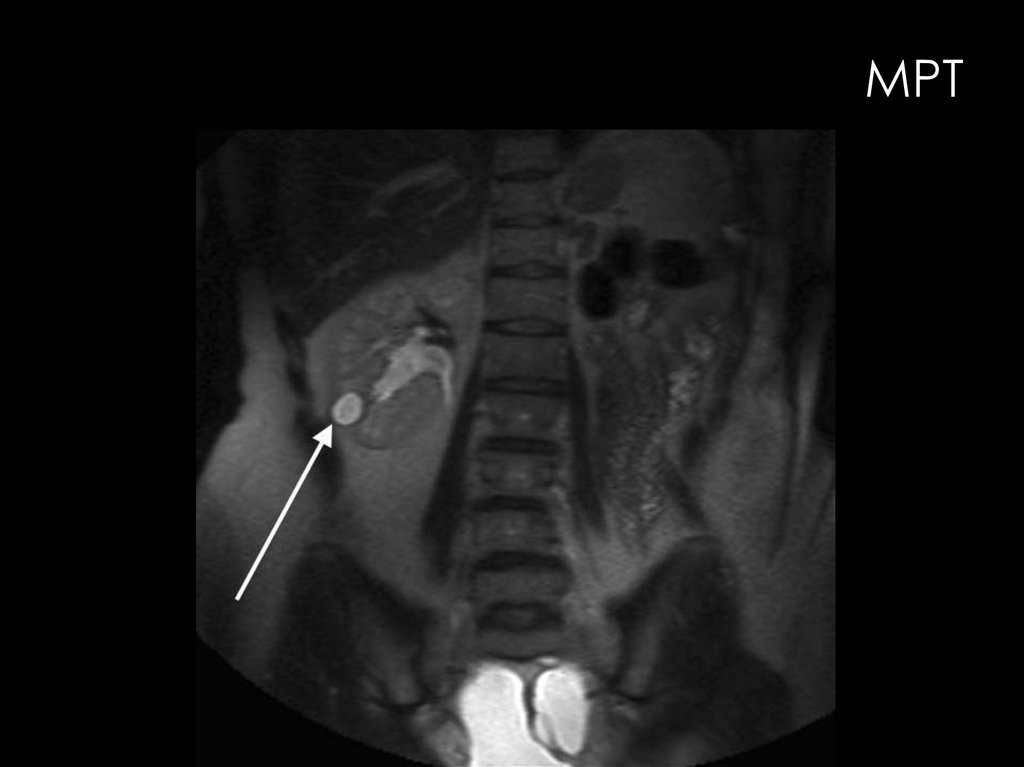

МРТ

Современные высокопольные МР-томографы обладают большими

возможностями визуализации и детальной характеристики всех

мочевых органов. Базовой методикой исследования мочевых

органов является нативная МРТ.

Возможности МРТ в диагностике заболеваний мочевых органов

значительно расширяются при использовании специальных

методик:

•МРТ с контрастным усилением

•МР-ангиография

•перфузионная МРТ.

•магнитно-резонансная

урография (МР-урография)